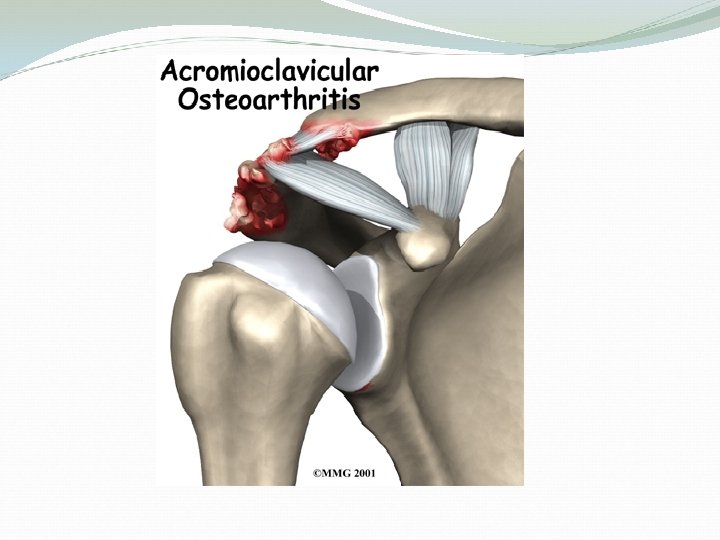

AC arthritis Arthritis is a condition characterized by loss of cartilage in the joint, which is essentially wear and tear of the smooth cartilage which allows the bones to move smoothly. Motions which aggrevate arthritis at the AC joint include reaching across the body toward the other arm.

Causes of AC osteoarthritis Degenerative osteoarthritis. ( wear and tear in old aged people) • Rheumatoid Arthritis • Gouty Arthritis • Septic Arthritis • Atraumatic osteolysis in weight lifters. ( result of repeated movements that wear away the cartilage surface found at the acromioclavicular joint) • Post-traumatic osteolysis of lateral end of clavicle. ( like dislocation or a fracture)